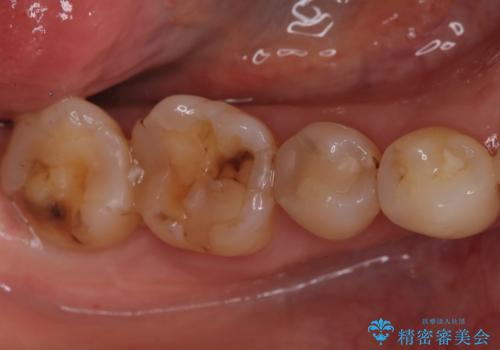

欠けやすい大きなプラスチック充填から、耐久性の高いセラミッククラウンへ

担当医 河口智英